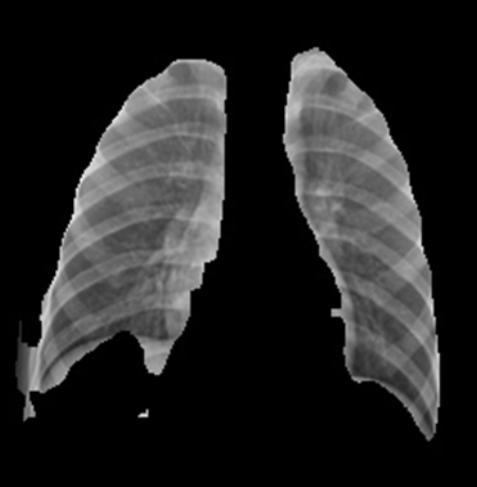

The initial critical stage in the hybrid architecture is the preciseisolationofthelungfieldsusingaspecializedU-Net model.TheU-Net’sprimaryroleistogenerateapixel-wise segmentation mask that accurately delineates the boundariesofthelungtissue.

Theoutputofthesegmentationmodelisutilizedtoproduce the definitive input for the classification stage. This segmentedimageiscreatedbymultiplyingtheoriginalX-ray pixelvaluesbythecorrespondingU-Netmask.Thisaction guarantees that the subsequent classification networks ResNet50 and DenseNet121 only receive pixels that are diagnosticallyrelevant,effectivelyrestrictingtheRegionof Interest (ROI) to the lung parenchyma. By meticulously isolatingthelungregion,thisstepsubstantiallyminimizes theinfluenceofirrelevantanatomicalfeaturesorartifacts, suchashigh-densitybonestructuresoutsidethelungarea. This deliberate isolation forces the model's feature extraction processtospecialize onthe subtle textural and densitypatternsassociatedwithconsolidationandopacity, leadingtobettersignaldetectionandfeaturedifferentiation betweennormalandinfectedlungs.

The integration of segmentation facilitates crucial interpretability.Figures10(PneumoniaSegmentation)and Figures9(NormalSegmentation)visuallyconfirmthehigh precisionoftheU-Netmodelinaccuratelyisolatingthelung parenchyma. This demonstrates that the classification modelswere indeed trained and testedexclusivelyon the relevantlungtissue.

Figure11illustratesthefinaloutputofthesystem,showing the prediction of pneumonia alongside its confidence probability. The successful visualization of the initial segmentation and the final prediction fulfills the core requirementformodelinterpretability.Thisvisualevidence serves as a critical proxy for explainable AI, significantly contributingtotheclinicalviabilityanduseracceptanceof thetool.